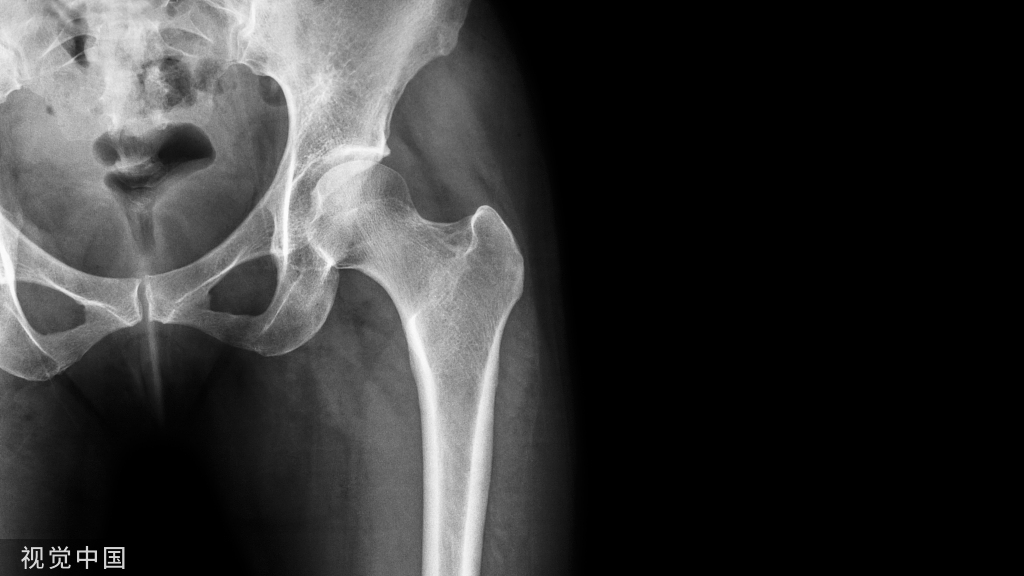

单侧双通道脊柱内镜技术(unilateral biportal endoscopic, UBE)下减压是治疗退行性腰椎管狭窄(degenerative lumbar canal stenosis, DLCS)的微创(minimally invasive, MI)手术方法。通过适当控制生理盐水的流入和流出,UBE可以在清晰、放大的手术区域内进行减压。